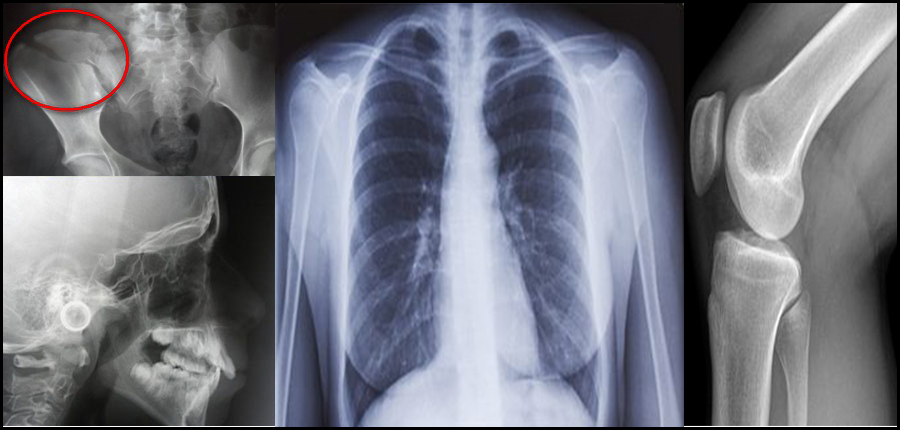

Quelles sont les possibilités techniques et réglementaires pour que l'imagerie médicale conventionnelle soit à la portée ?

Dr Mohammed RHAZOINI

Quelles sont les possibilités techniques et règlementaires pour rapprocher l’imagerie médicale du patient Marocain ? Pour répondre à cette question, une journée de réflexion multidisciplinaire a été organisée récemment par des médecins spécialistes Marocains appartenant à quatre associations de spécialités médicales et chirurgicales. Pour parvenir à des solutions réalisables, ils ont procédé à un Benchmark avec plusieurs pays d'Europe et des USA. Evolution médico-technologique et volet règlementaire sont passés au peigne fin. L'Objectif de cette approche et d’étudier les meilleurs moyens de rendre service au patient marocain dans le respect de la loi et de la déontologie.

L’imagerie médicale entre évolution technologique et intérêt des patients

Miniaturisation et moins d’irradiation des appareils de nouvelle génération de l’imagerie médicale, ce qui ouvre plus large le champ à des utilisations spécifiques. Utilisation plus fréquentes de l’imagerie médicale dans des situations médicales bien précises, par les médecins spécialistes d’organes, dans des pays comme la Belgique, la France, la Suisse ou les Etats-Unis d’Amérique (USA). Nécessité urgente de l’actualisation de la réglementation en vigueur au Maroc.